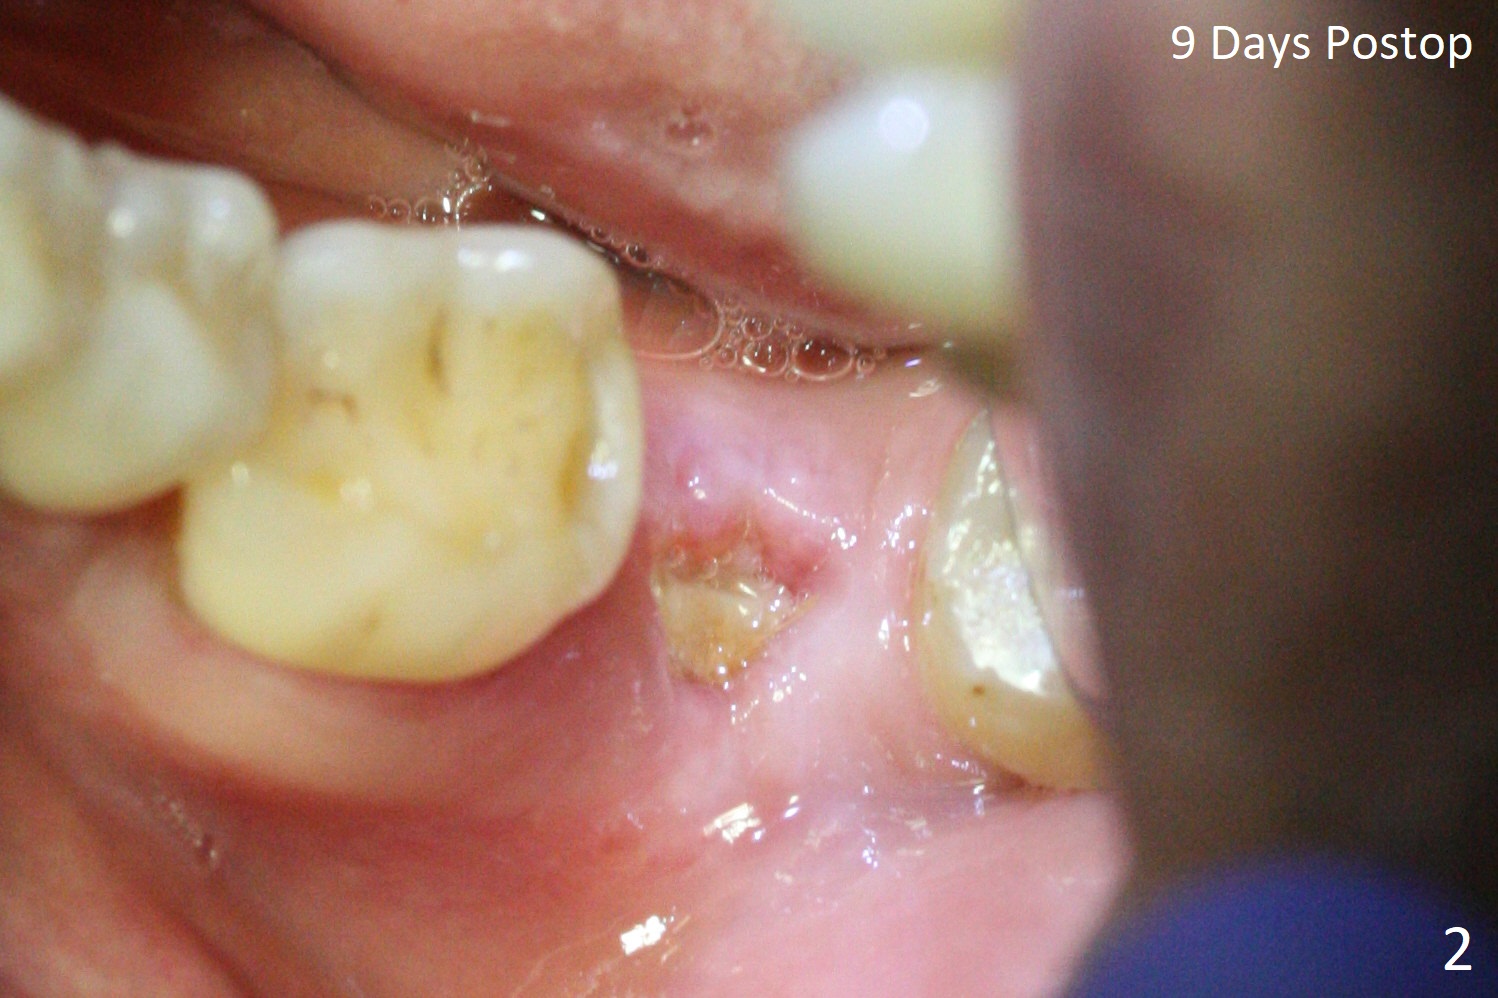

A 49-year-old man returns for #14 and 15 implant impression. The tooth #18 is buccally shifted with mobility, which is incompatible with #14 and 15 restoration. The tooth has to be extracted with socket preservation (Fig.1). A piece of 6-month collagen membrane is used to cover allograft. The socket is healing 9 days postop (Fig.2), probably related to its small wound. Three months and a half postop (Fig.3), CT shows bone healing (Fig.4 sagittal (thin) section, 5 (thick section); 6 (coronal (thin) section). A 5x8.5 mm implant will be placed (Fig.7,8).